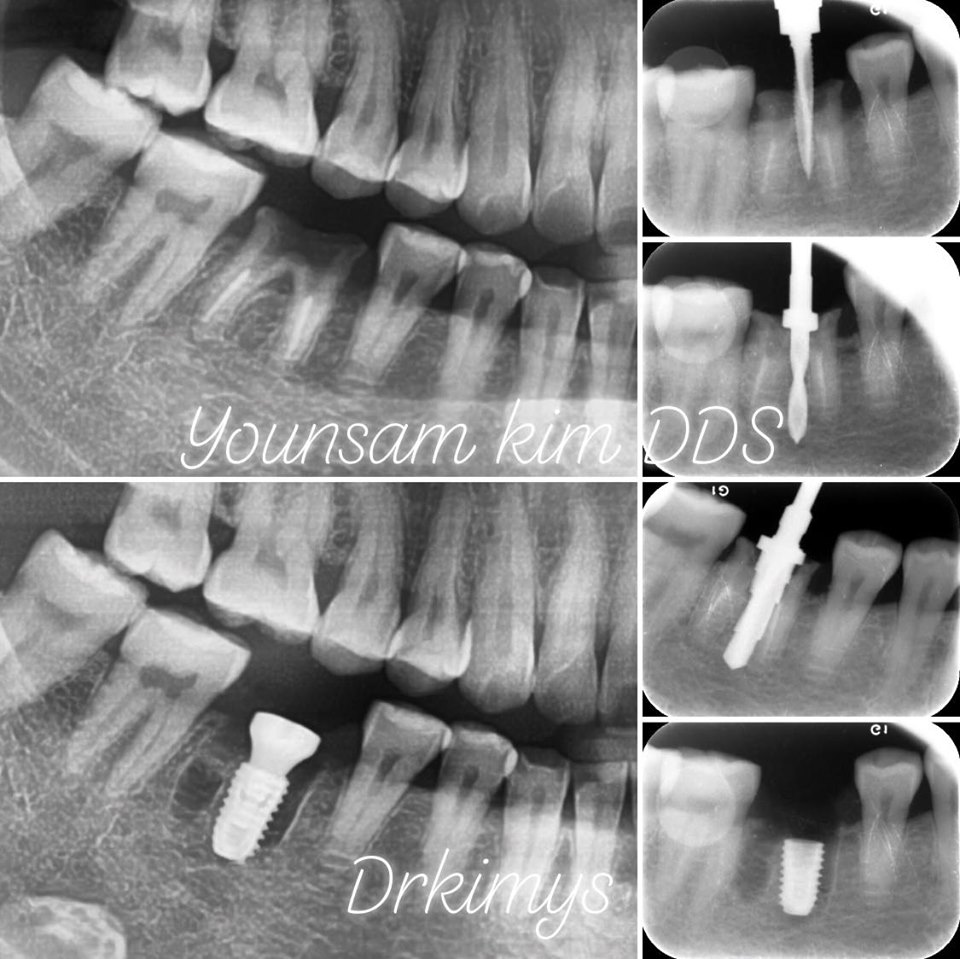

많은 사람들이 이렇게 알고 있는데 사실 발치 즉시 식립이라고 불리는 수술이죠. 얼마 전에 사랑니를 뽑으러 오셨다가 그 앞에 있는 큰어금니까지 뽑은 케이스가 있었어요. 누워서 난 사랑니가 앞 어금니의 중간과 뿌리 부분에 충치를 발생!! 이 대구치는 기존에 신경치료를 받은 경험이 있어 통증을 느끼질 못했던 거죠. 우식증이 커질대로 커지고 심지어 뿌리쪽까지 진행이 되어서 도저히 살리기 힘든 경우였지요. 참 안타깝죠. 신경치료를 한 이는 문제가 생겨도 아프지 않아서 이렇게까지 방치 되기 정말 쉬워요. 그래서 꼭 3~6개월에 1번씩 정기검진을 가는 게 중요하죠. 틈틈히 체크를 해서 충치를 초기에 발견했다면 사랑니 뽑고 다시 치료할 수 있었을텐데.. 결국 사랑니와 함께 제2대구치 발거 판정을 받을 수밖에 없었죠. 그치만, 이렇게 뽑은 날 원데이로 임플란트 수술까지 하기로 하였습니다. 심을 때 원래 치근의 방향, 각도대로 심어주는 것이 핵심이죠. 그래야 추후에 인공보철물이 올라갈 때 기존의 자연치처럼 좋은 위치로 셋팅될 수 있죠. 저희 원장님께선 공간감각이 워낙 좋아서 여러 개를 심어도 픽스처 각도가 완벽! 다음엔 여러 개를 한꺼번에 심은 사례를 준비해 소개할께요.

강남레옹치과에선 요즘 이런 사례에선 종종 발치 즉시 식립을 해요. 임상경력이 워낙 많아 이럴 땐 잇몸이 아물은 후에 심는 것과 큰 차이가 없다는 생각이시죠. 전에는 잘 안하셨는데 1차 안정성도 그렇고 깊이가 잘 조절되는 한 요즘은 원데이를 더 선호해요. 저희 의료진은 자연치아를 누구보다 아껴서 왠만하면 살려주는데도 딱 봤을 때 이건 아니다 싶을 때만 이런 결정을 내리신거죠. 얼마 못가 치아 머리가 똑 하고 파절되어 탈락이 될 가능성이 정말 크기 때문이에요.

또 한 케이스. 이분은 이미 치관이 부러졌습네요. 남은 뿌리를 제거하고 그 자리에 고정체를 심었죠. 그 주변으로는 조직이 잘 아물도록 도움을 주는 치유지혈보조제를 넣습니다. 보통 사랑니를 뽑을 때 쓰는데 이렇게 절개를 하지 않고 바로 심은 경우에도 사용을 하죠. 치유에 정말 도움이 많이 된다 생각이 드네요.

많은 사람들이 아직도 임플란트 수술을 부담스러워 하는 이유 중 하나가 바로 긴 기간일거에요. 이를 뽑고 잇몸이 아물기까지 2~3개월 정도를 기다려야 되고, 픽스쳐를 심으면 또 유착될 때까지 기다리고.. 기다림의 연속이죠^^ 그치만 치아를 뽑고 당일에 픽스쳐를 심는다면 내원 횟수랑 총 치료기간이 많이 줄어들겠죠?? 물론 모든 증례에 다 적용이 되는 방법은 아니에요. 치주질환으로 이미 염증이 심하거나 치조골이 부족한 경우에는 진행이 어렵죠. 전문의의 소견이 중요하게 작용하는 부분이라 충분하게 상담을 하고 결정하는 게 좋아요. 저번 달에 소개했던 상악동 거상술을 동반한 증례처럼 뼈이식이 많이 들어가면 발치 즉시 식립은 불가능하지요.